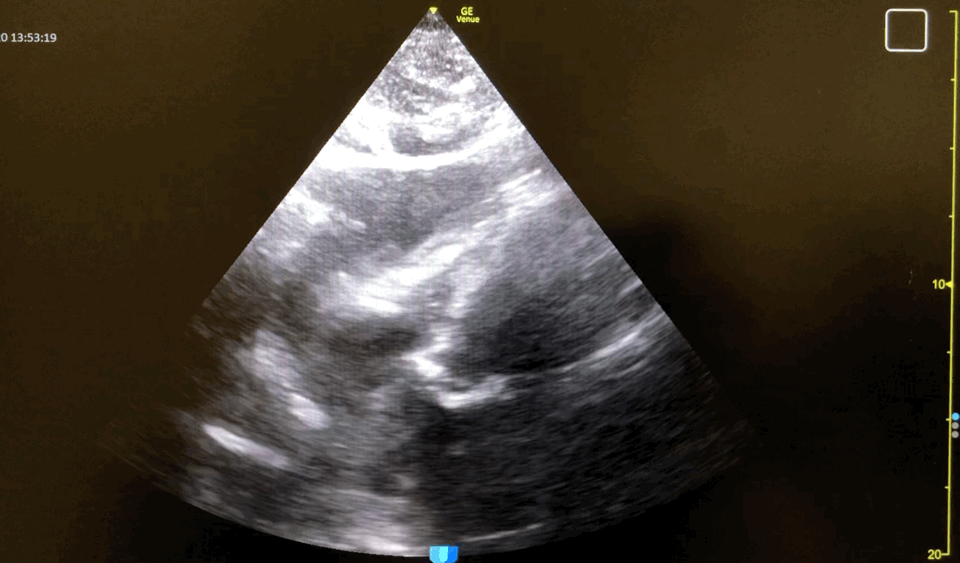

SC

SC view showing large pericardial effusion compromising right ventricular filling: This SC view displays a large pericardial effusion that is significantly compromising the filling of the right ventricle. The large anechoic (black) fluid collection around the heart is exerting pressure on the right side, limiting its ability to fill properly during diastole, which is a critical sign of approaching tamponade.